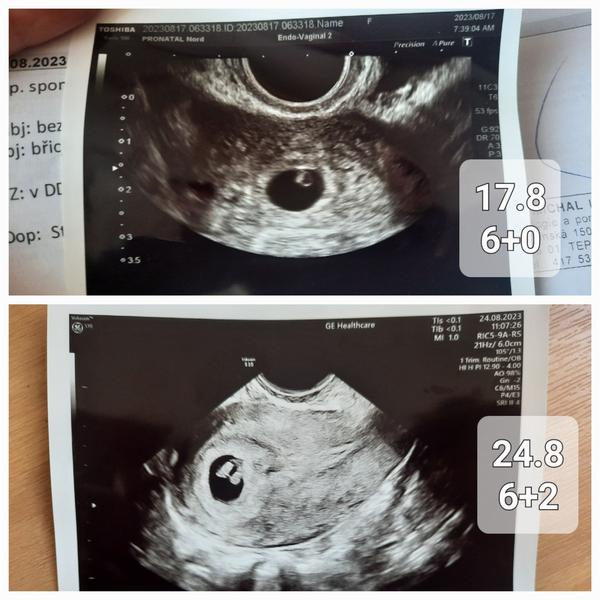

Ahoj holky, pomoc! Zacinam silet. Minuly tyden ve čtvrtek jsem byla na prvnim ultrazvuku v Pronatalu a ten vyplyvl crl 6+0. Tento ctvrtek jsem mela byt tedy tim padem 7+0 a jiný lékař, jiný ultrazvuk (v nemocnici) řekl 6+2. Tak jsem z toho na palici, ze je neco špatně. Akce srdecni je, to je důležité. Jen mám strach, že se špatně vyvíjí a pripravuju se na nejhorsi (mam za sebou zamlkle tehotenstvi a nekolik let snazeni) :( máte někdo zkušenost ?

Pozn. 14.8 hcg 2261, 24.8 33675